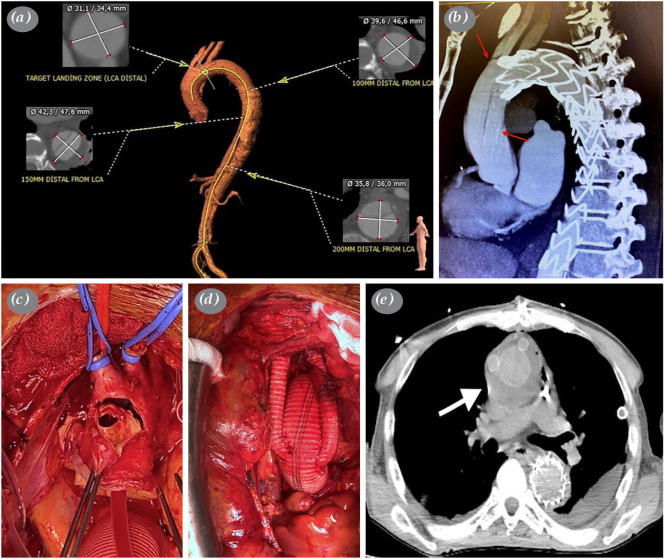

由于与开放手术相关的高死亡率和发病率,对于复杂的急性B型主动脉夹层患者,通常首选血管内治疗方法。逆行主动脉夹层是一种罕见的血管内手术并发症。在此,我们报道了一名53岁男性患者的手术治疗逆行主动脉夹层,该患者两年前有肝移植史并服用免疫抑制药物。

Endovascular treatment methods are often preferred in suitable patients with complicated acute type B aortic dissection due to the high mortality and morbidity associated with the open surgical procedure. Retrograde aortic dissection is a rare complication of endovascular procedures. Herein, we reported surgical treatment of a retrograde aortic dissection that developed after thoracic endovascular aortic repair in a 53-year-old male patient with a history of liver transplantation two years ago and taking immunosuppressive medication.